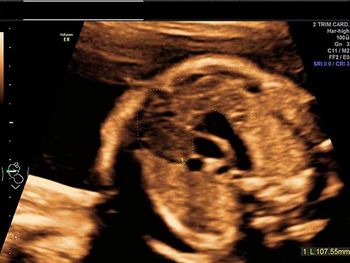

Challenge your diagnostic skills: Can you identify this anomaly of the fetal face and brain?